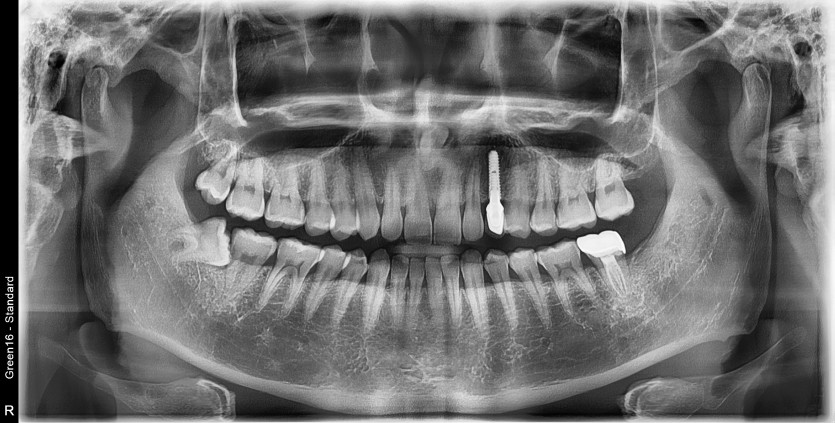

#18,48 사랑니 발치

구강 외과 전문의가 당일 발치했습니다.